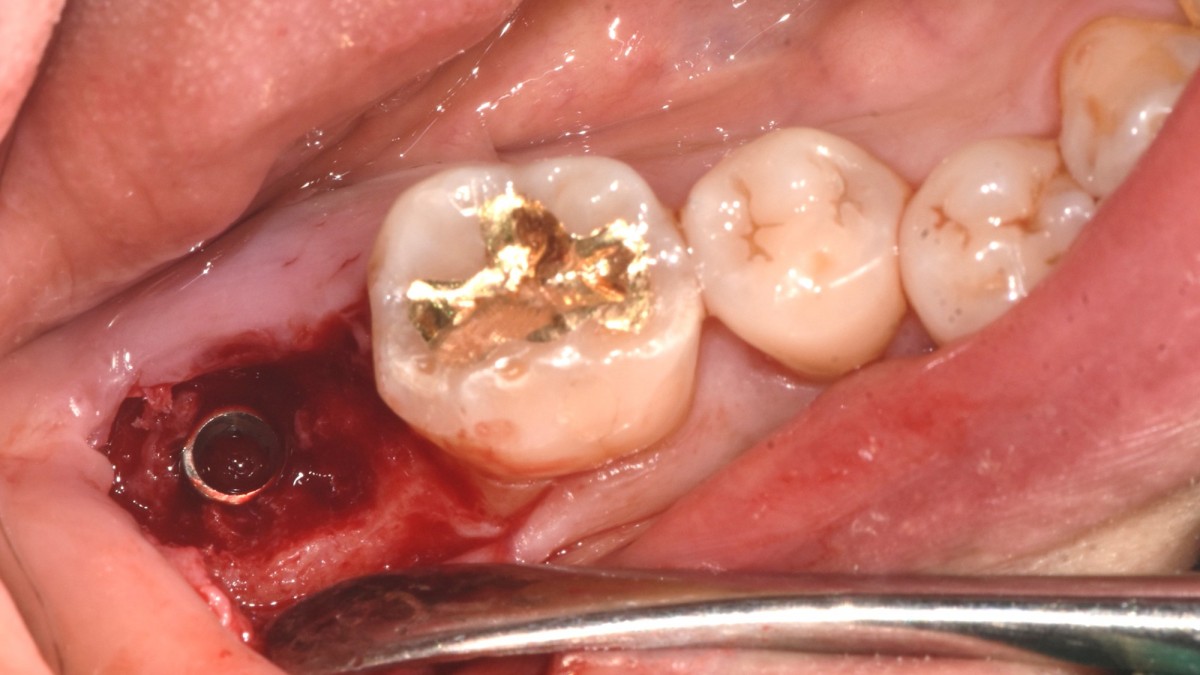

A 47-year-old male patient had a crown with an ill-fitting margin and crack-tooth syndrome in the lower 2nd molar. No systemic issue.

▲extraction

▲Arum Dentistry NB1 5*10